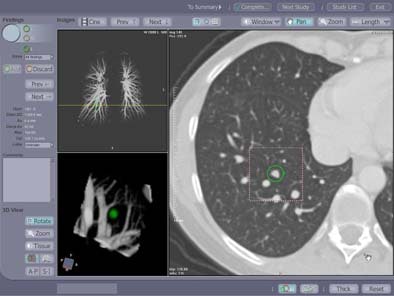

|

| Contrast enhanced spiral CT study in a 49-year-old woman with a history of colon cancer. A 7-mm soft tissue lung lesion was missed at clinical interpretation but detected by CAD. The location of the lesion in the immediate vicinity of lung vessels of similar size may have prevented its detection at the initial readout. A yellow line indicates the anatomical level of the displayed section within the volume data set in a coronal maximum intensity projection of the pulmonary vascular tree (left upper image panel). 3D volume rendering (left lower image panel) of the lesion highlighted in green displays the spatial relationship of the lesion relative to surrounding vascular structures and enables better differentiation of focal lung lesions and vessels than individual axial sections. Image courtesy of Dr. Joseph Schoepf. |

|